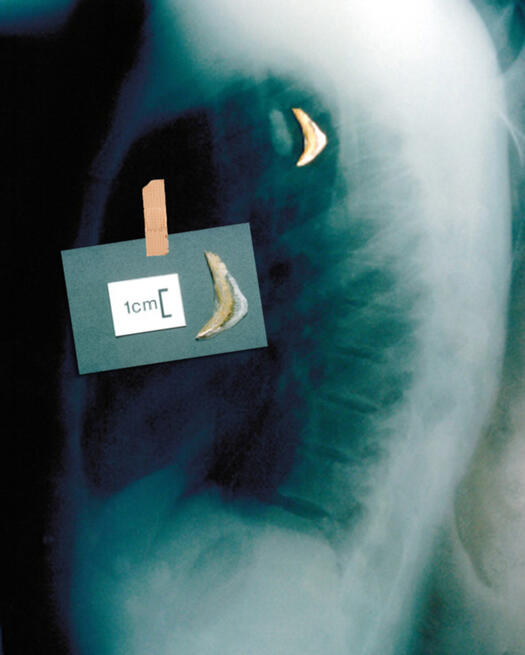

ЕКСПОНАТ 4

Рибена кост

Пак Великобритания. Явно етикетът там да се яде рибата с нож и вилица не води до нищо хубаво...